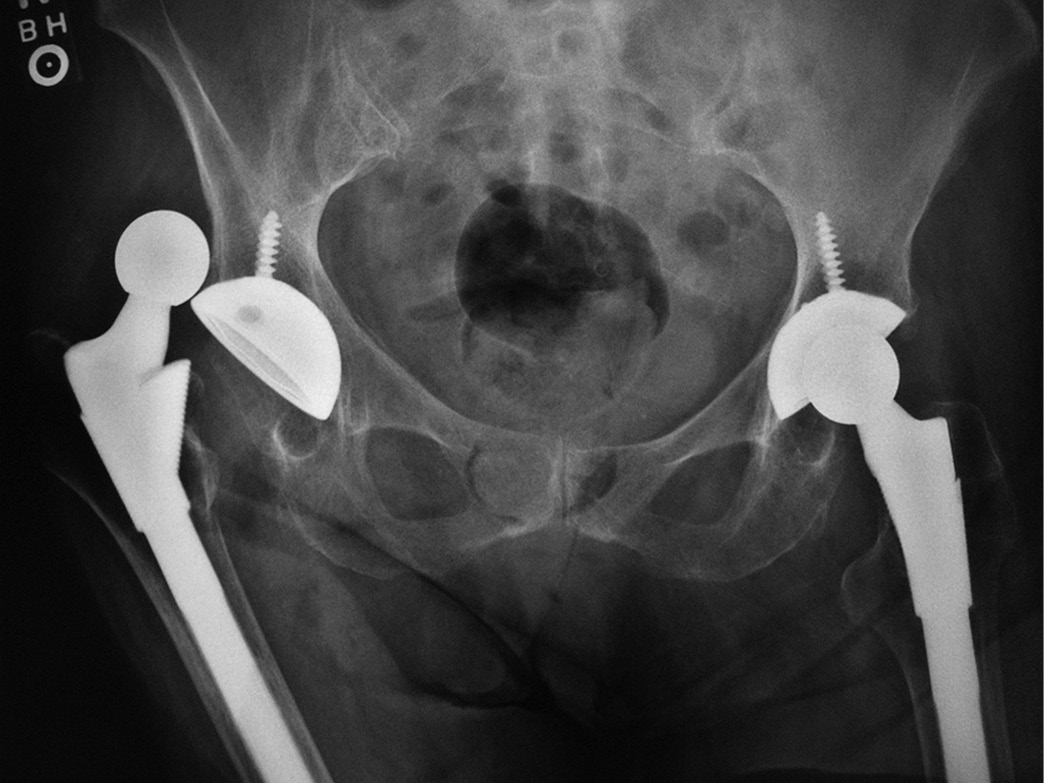

Эндопротезирование тазобедренного сустава: фото и схемы

:max_bytes(150000):strip_icc()/x-ray-illustration-of-hip-replacement-1254389829-281a949198324333972a407cc2e90760.jpg)